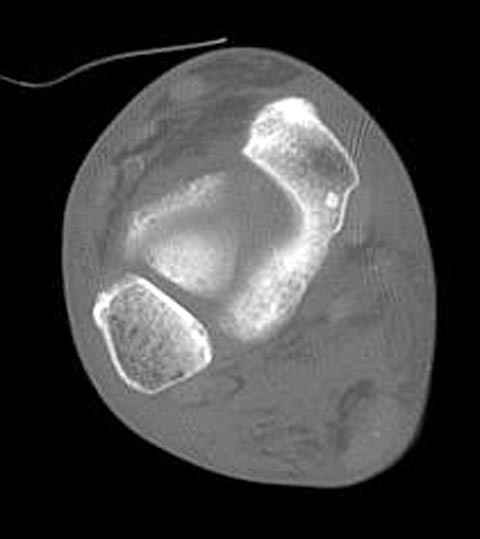

Уважаемые участники русского Ортофорума, поздравляю всех со всеми прошедшими праздниками: Новым годом, Рождеством, Hanukkah, Kwanzaa, желаю участникам всего наилучшего и здоровья.Повреждение таранной кости.Больной 81г автоавария, повреждение таранной кости, здесь снимки. Какие рекомендации?Djoldas Kuldjanov, MDDepartment of Orthopedic SurgerySt. Louis University Medical Center

Вдогонку по поводу перелома таранной кости, больная 81, не страдает диабетом, перелом закрытый, в первый же день поступления ограничились временным наружным фиксатором (как на снимке).

Планировалась открытая фиксация после спадения отека, но больная пожелала лечиться по месту жительству в другом штате..

За пару недель насчитал 5 больных с переломом таранной кости, из них двое с двусторонним повреждением.

Из-за отека на стопе тактика лечения у всех была

одинаковая: временная наружная фиксация до спадения отека, при изолированных переломах они выписывались домой и через дней 7 госпитализировались на оперативное лечение.

Примеры на снимке...